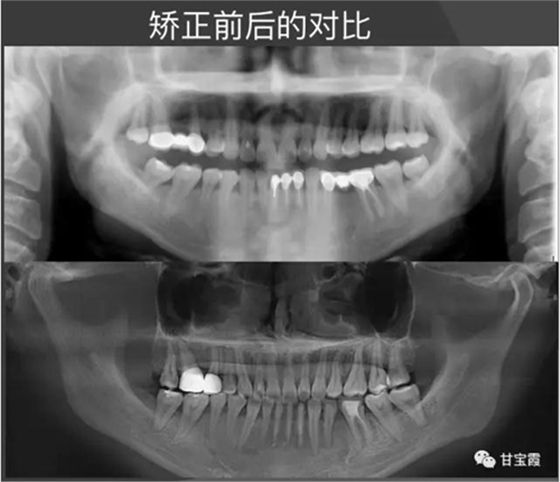

經(jīng)過(guò)28個(gè)月的矯正,大家可以看到原來(lái)的兩個(gè)缺牙間隙沒(méi)有了,舊的烤瓷牙換成了全瓷冠修復(fù)。下面的圖片是矯正前后的X線(xiàn)對(duì)比,